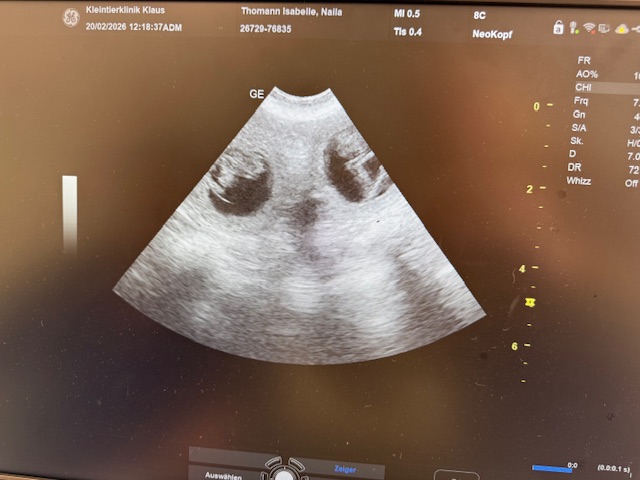

Wir planen mit Naila einen Wurf auf ca. Ende März 2026 und sehr bald geht es auf Reisen….

23. Januar 2026 Naila von der Wieselweide hatte ein Date bei Billsor Rough Diamond (Michi) und nun hoffen wir auf hübsche blauschimmel Welpen.